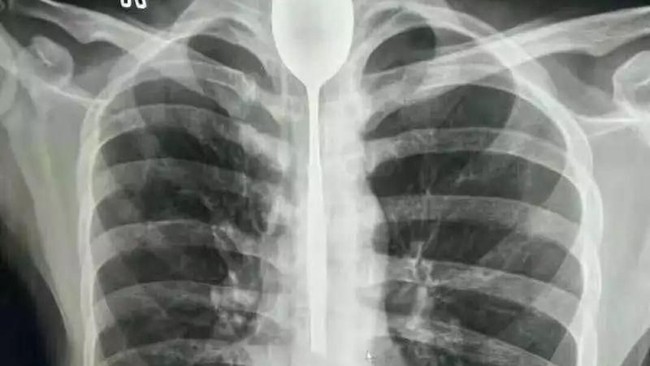

"Vijay dibawa ke rumah sakit sekitar 15 hari yang lalu, dan dari pemeriksaan X-ray, kami temukan benda logam di usus besarnya. Ketika saya menanyakan hal ini ke pasien, Vijay mengaku bahwa dia dipaksa untuk menelan sendok-sendok tersebut. Akhirnya kami lakukan tindakan operasi selama dua jam, tapi kami belum pernah melakukan operasi seperti ini sebelumnya," tutur Dokter Rakesh.

Bentuk sendoknya juga bukan sendok utuh. Melainkan Vijay harus mematahkan kepala sendok, dan yang dimakan hanya bagian gagang sendoknya saja.

Untungnya nyawa Vijay masih bisa tertolong. Ia kini masih berada di ICU, dan dalam proses pemulihan usai 63 sendok dikeluarkan daari perutnya.